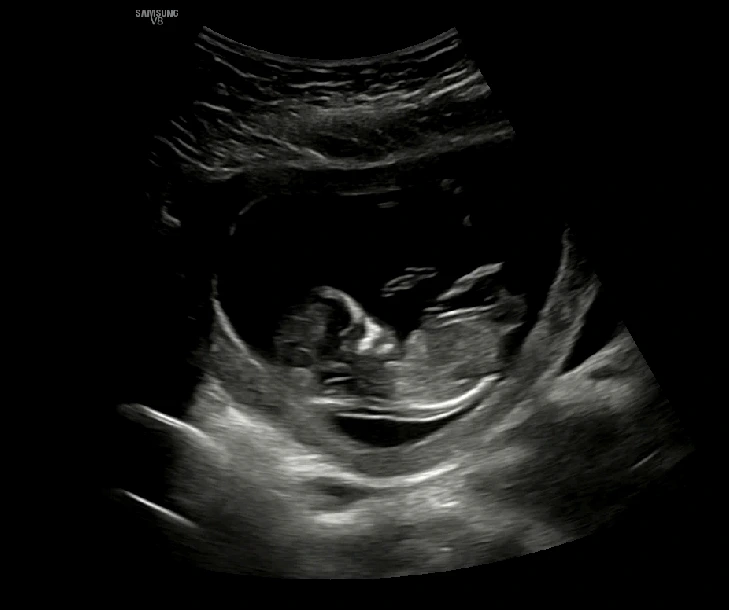

임신 12주차 초음파

임신 12주차 초음파 사진! 이때부터 내가 아는 사람의 모습을 한 형태가 보이기 시작했다.ㅎㅎ 너무너무 신기해! 이때까지만 해도 딸이든 아들이든 상관없다고, 다 감사하다고 생각했는데 점점 딸일지 아들일지 궁금해지기 시작했다. 굳이 굳이 성별을 뽑아보자면 나는 아들, 남편은 딸을 선택해보았다.